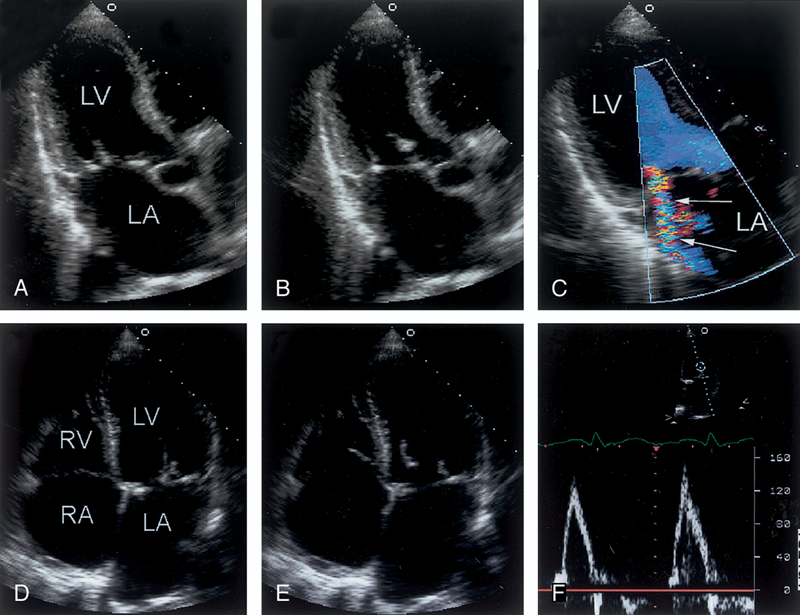

فحوصات تشخيصية لبعض امراض القلب والشرايين التاجية